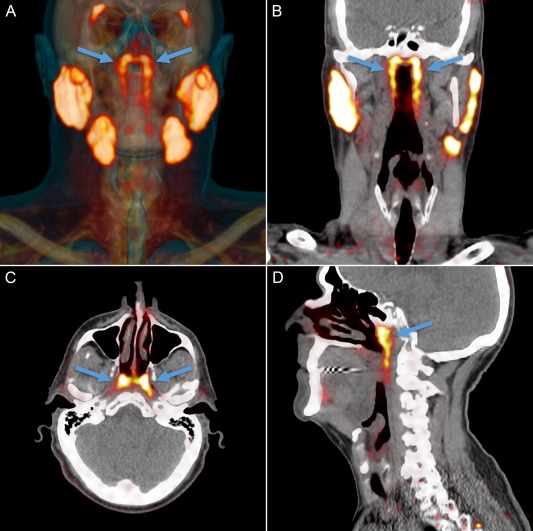

Aceștia au observat noua glandă în timp ce studiau mai mulți pacienți cu cancer de prostată, folosind scanarea PET/CT PSMA (adică Positron Emission Tomography / Prostate-Specific Membrane Antigen).

Astfel, după ce au scanat 100 de pacienți și după relizarea a două disecții, cercetătorii au putut confirma prezența acestei noi glande la om, de aproximativ 3,9 centimetri lungime (în medie).

În articolul publicat în revista The Green Journal, echipa a propus denumirea de „glande salivare tubare” având în vedere că le-au descoperit așezate precum o „draperie” peste torus tubarius – porțiunea bazală cartilaginoasă a trompei lui Eustachio. Și, după cum susțin cercetătorii, aceste glande au în medie aproximativ 3,9 centimetri lungime.